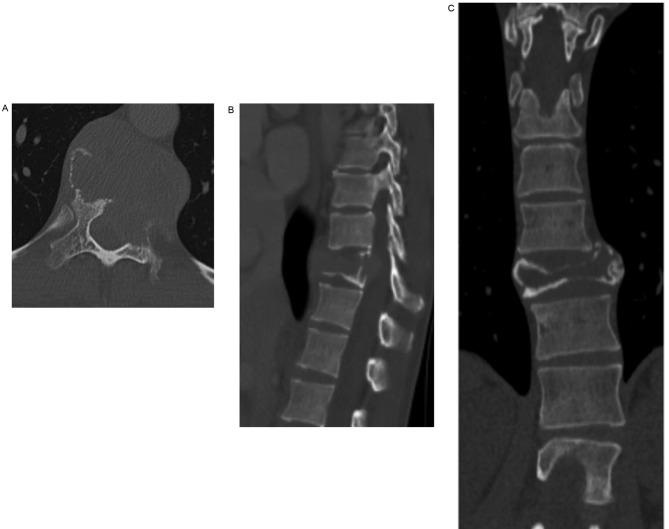

Although denosumab has been reported to induce effective clinical results with respect to tumor shrinkage in a short-term follow-up clinical study, total spondylectomy is recognized as the treatment of choice for eradicating giant cell tumors (GCTs) of the spine. The present study reports the case involving a GCT in the 11th thoracic vertebra complicated by idiopathic scoliosis and treated using total en bloc spondylectomy (TES) with preoperative denosumab therapy. A 35-year-old woman received preoperative denosumab therapy for 8 months, followed by surgery using a computed tomography (CT)-based navigation system that optimized accuracy by recognizing the area of the detached parietal pleura, the irregular border of the collapsed vertebra, and the adjacent vertebra. Complete en bloc resection of the vertebra could be performed, suggesting denosumab can be an effective adjuvant therapy which can reduce the complexity of TES and CT-navigation system facilitated the safe use of this surgical method in a patient with idiopathic scoliosis.

尽管在一项短期随访临床研究中,已报道地诺单抗在肿瘤缩小方面可产生有效的临床效果,但全脊椎切除术被认为是治疗脊柱骨巨细胞瘤(GCT)的首选方法。本研究报告了一例第11胸椎骨巨细胞瘤合并特发性脊柱侧凸的病例,该病例采用术前地诺单抗治疗后行整块全脊椎切除术(TES)。一名35岁女性接受了8个月的术前地诺单抗治疗,随后使用基于计算机断层扫描(CT)的导航系统进行手术,该系统通过识别分离的壁层胸膜区域、塌陷椎体的不规则边界以及相邻椎体来优化准确性。椎体能够被完整整块切除,这表明地诺单抗可以作为一种有效的辅助治疗方法,它能够降低TES的复杂性,并且CT导航系统有助于在患有特发性脊柱侧凸的患者中安全使用这种手术方法。